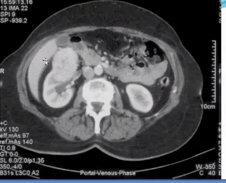

CT urogram (contrast enhanced urogram to check for abnormality in kidney parenchyma)/KUB US

Renal cell ca from cortext of the kidney

Iff transitional it would be from the pelvis

bilateral hydronephrosis